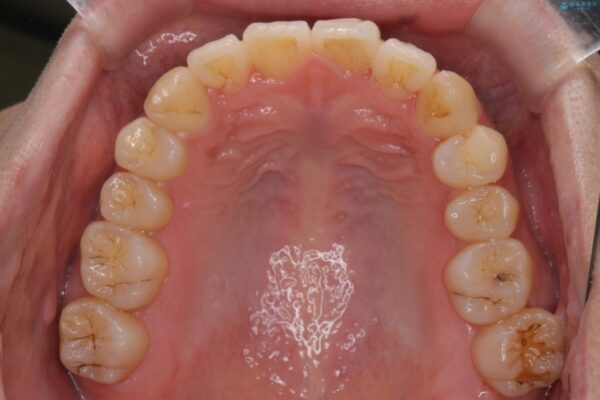

治療後

気になる犬歯のガタつきをマウスピース矯正で改善 治療後画像 気になる犬歯のガタつきをマウスピース矯正で改善 治療後画像 気になる犬歯のガタつきをマウスピース矯正で改善 治療後画像 気になる犬歯のガタつきをマウスピース矯正で改善 治療後画像